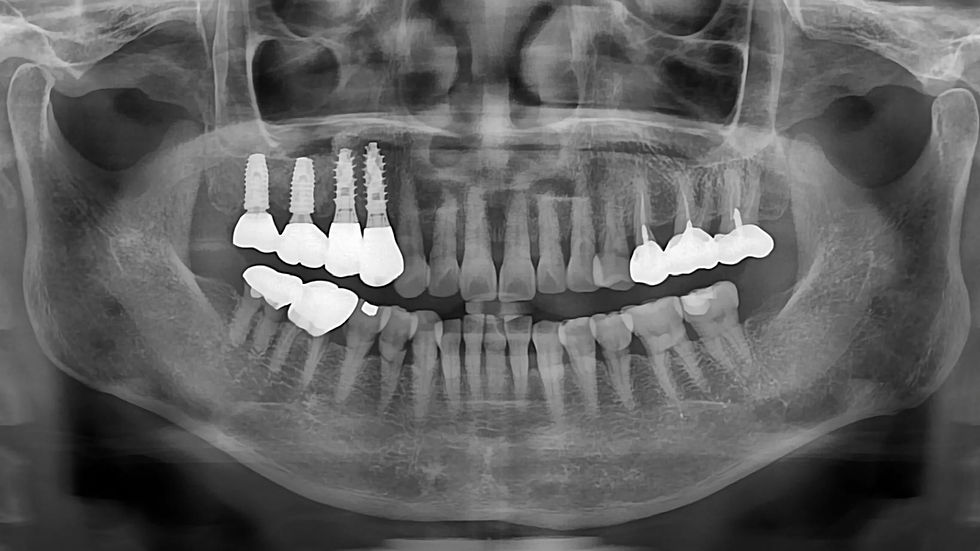

This case describes the immediate placement of two implants in the posterior maxilla (#14 and #15) following tooth extraction. At site #15, a crestal sinus elevation was performed due to insufficient residual bone height. The ALX system was used for implant placement, providing excellent primary stability. This enabled early functional loading within just one month after surgery. This case highlights a predictable and efficient approach for managing posterior maxillary sites with simultaneous extraction, sinus grafting, and accelerated prosthetic restoration.

1️⃣ Pre-Op

Tooth #15 was located in close proximity to the maxillary sinus floor, and residual bone height was insufficient—indicating the need for sinus augmentation.

The loss of lamina dura indicated a hopeless prognosis, supporting the decision for extraction and immediate implant placement.